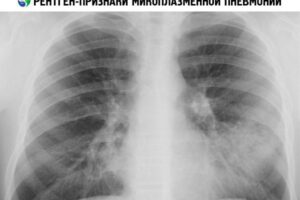

Особенности диффузной милиарной пневмонии

Диффузная миллиардная пневмония — это разновидность пневмонии, характеризующаяся образованием миллиардных очагов инфильтратов в легочной ткани, образующих ретикулярную структуру. Эти пневмонии являются тяжелыми и хроническими, воспаление быстро распространяется на все легкое и в некоторых случаях бывает двусторонним. Диффузное поражение легких приводит к развитию фиброза и выраженной дыхательной недостаточности. Этиология (причины) Для развития столь тяжелого заболевания необходимы …